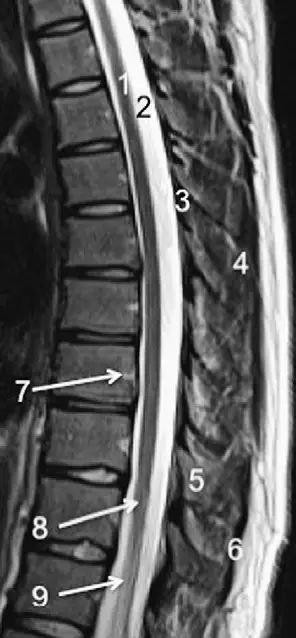

图 6 胸椎 T1WI 序列成像:1,胸髓;2,蛛网膜下腔;3,硬膜外脂肪;4,黄韧带;5,多裂肌;6,棘突;7,硬膜外静脉;8,棘上韧带

图 7 胸椎矢状位 T2WI 序列成像:1,胸髓;2,蛛网膜下腔;3,黄韧带;4,多裂肌;5,棘突;6,棘上韧带;7,椎体静脉;8,脊髓圆锥;9,马尾

图 8 胸椎旁矢状位 T2WI 序列成像:1,硬膜囊后壁;2,硬膜外脂肪;3,黄韧带